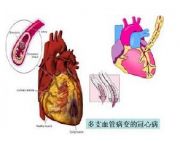

| 2021年7月26日 (一) 20:03 | 易损斑块.jpg (文件) |  |

23 KB | Uploaded with SimpleBatchUpload | 3 |

| 2021年7月26日 (一) 20:03 | 心脏搭桥手术.jpg (文件) |  |

26 KB | Uploaded with SimpleBatchUpload | 3 |